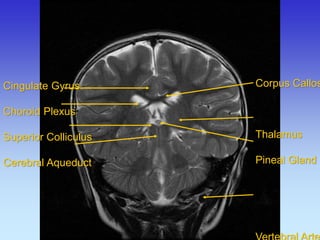

Cingulate Gyrus Choroid Plexus Superior Colliculus Cerebral Aqueduct

Corpus Callosum Thalamus Pineal Gland Vertebral Artery